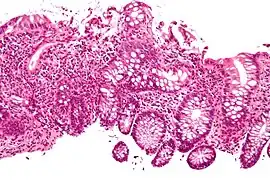

Crypt abscess. H&E stain.